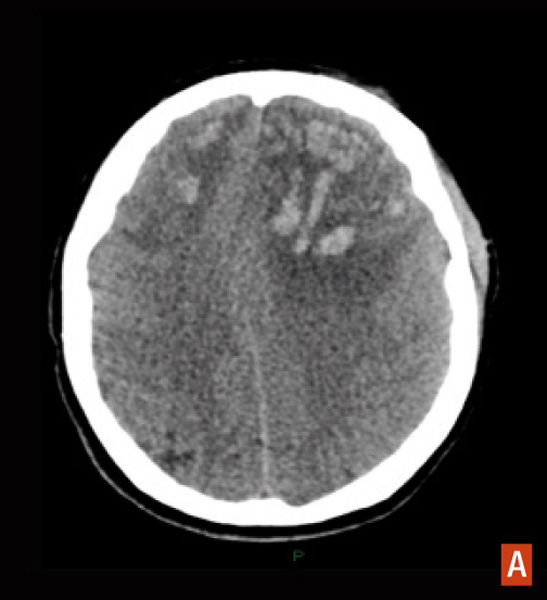

Hématome lobaire frontal bilatéral, secondaire à une thrombose veineuse du sinus sagittal supérieur. Hyperdensité spontanée associée à un oedème avec effet de masse, TDM cérébrale sans injection.